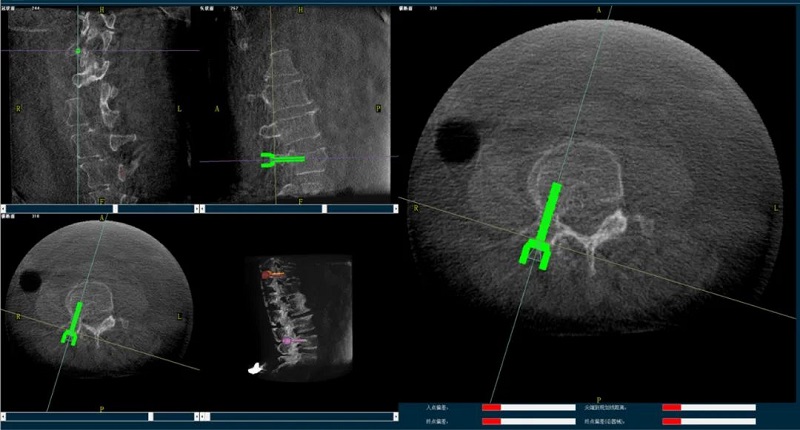

(2)醫(yī)生制定個(gè)性化的手術(shù)方案,在機(jī)器人導(dǎo)航界面上進(jìn)行路徑規(guī)劃;

(3)根據(jù)設(shè)定好的的位置和入針方向,植入引導(dǎo)針;